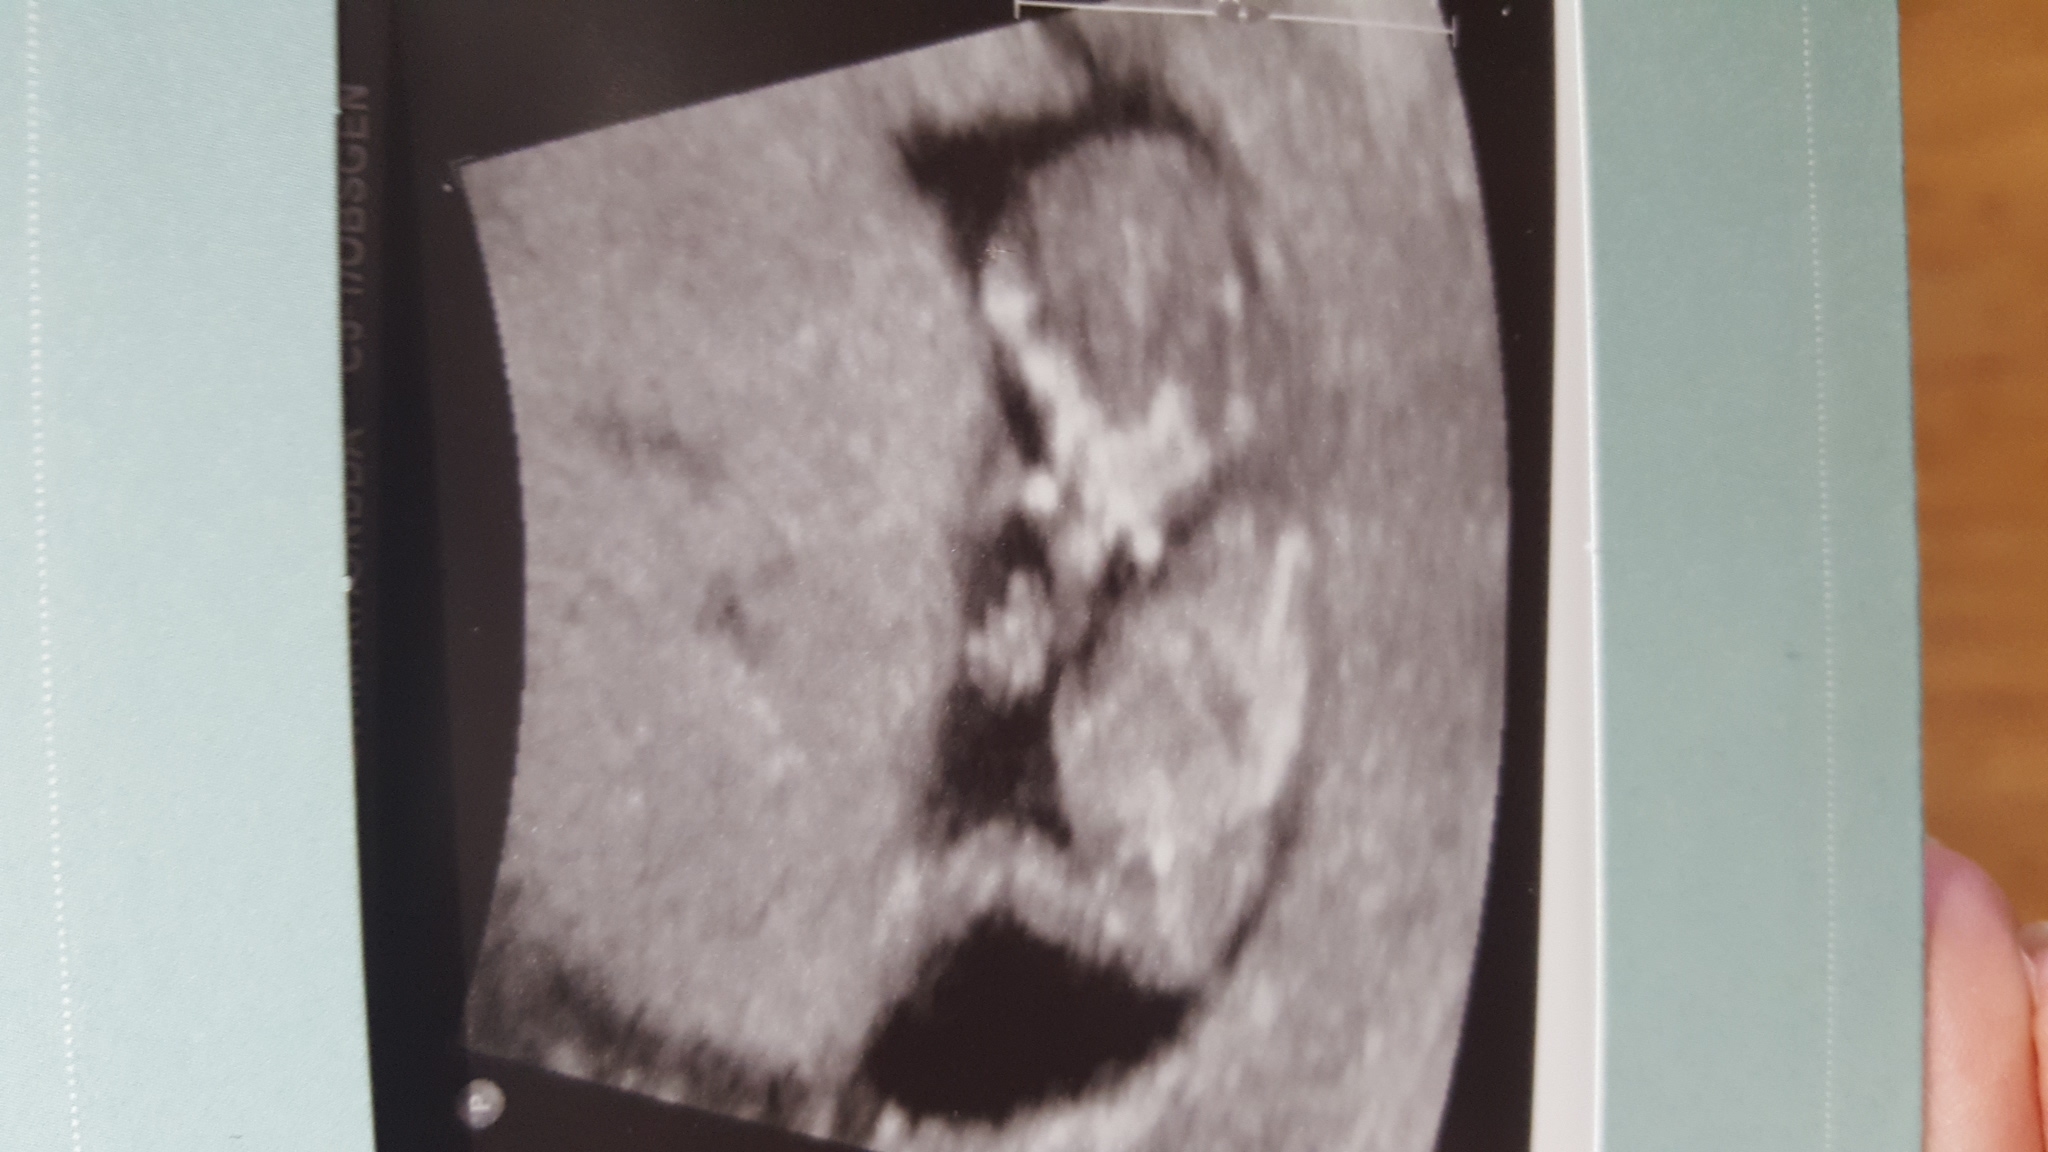

Any guesses on gender? We find out tomorrow 😊 scan was at 12 weeks exactly. Thanks for looking.Attachment 32752Attachment 32753

Not great clues but gonna guess girl off of pic 2 :)